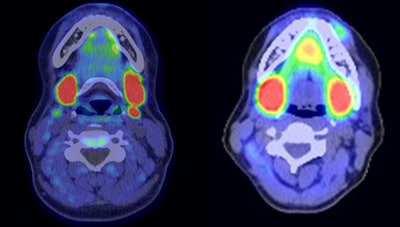

PET/CT imaging with carbon-11 (C-11) choline can help achieve surgical cures for patients with primary hyperparathyroidism after standard imaging approaches have failed, according to a study published October 11 in the journal Surgery.

Endocrine surgeons at the Mayo Clinic in Rochester, MN, explored whether C-11 choline PET/CT could identify abnormal parathyroid glands in patients who required further treatment after standard imaging and prior surgeries. The approach led to curative surgeries in 80% of patients, they found.

In 2012, the Mayo Clinic received U.S. approval for the use of C-11 choline PET for restaging biochemically recurrent prostate cancer and noted in case reports that the C-11 choline radiotracer also appeared to accumulate in hyperfunctioning parathyroid cells. The group has since shown that the approach performs well compared to standard imaging approaches in hyperparathyroid patients prior to surgery.

The researchers reviewed outcomes for 43 patients who received a C-11 choline PET/CT scan between 2017 and 2021 at the Mayo Clinic. Ultrasound, I-123 sestamibi, and 4D CT had failed to localize the disorder in most patients and 70% had prior operations at outside institutions. C-11 choline radiotracer was produced at the hospital's onsite cyclotron facility.

Out of the 43 patients, 33 (77%) had positive C-11 choline PET/CT findings, according to the results. Twenty-five patients proceeded to surgery, and of these patients, 20 (80%) achieved an intraoperative cure. Notably, 18 of the patients who proceeded to surgery (72%) had failed prior operations, the authors wrote. One patient had four prior failed operations, and five patients had two prior failed operations.